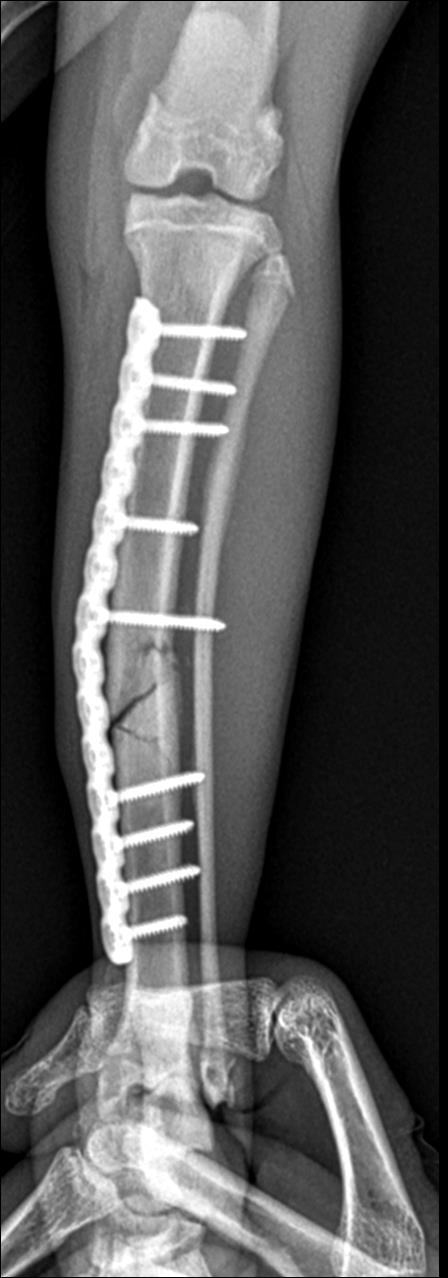

플레이트로 고정하는 수술이었는데 플레이트의 수명이 20년 정도라 추후에 이상만 없다면 반영구적으로 고정하게 된다고 합니다.

다행이 수술은 잘 진행되었고 추후에 뼈가 붙는 과정이 관리가 매우 중요하다고 해서 임시 보호에 신경을 많이 쓰게 되었습니다. 넥카라를 하며 다른 고양이들과 격리하여 베란다에서 지내게 되었고 다리에 위험이 되는 공간은 치워주었습니다.

매주 붕대를 교체해주며 엑스레이로 뼈가 붙는 과정을 지켜보았습니다. 고양이의 경우 사람처럼 완전히 고정되는 깁스를 할 수 없어 붕대를 여러 번 교체해 주어야 했습니다. 다람이가 순한 편인데도 매주 병원을 가다 보니 어느 순간 케이지에 안 들어가려고 해서 병원 데려가는 것에 어려움이 좀 있었습니다.

그렇게 2달여간의 치료 끝에 붕대를 풀게 되었고 그 사이에 예방접종과 동물 등록을 함께 진행하였습니다.